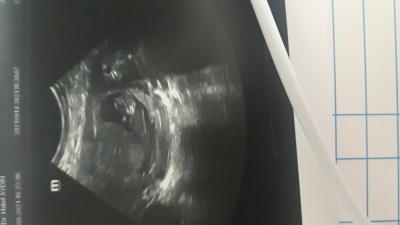

merhaba hanımlar 1 oglum bir kizim var tekrar hamileyim cok merak ediyorum cinsiyetini tahmin yaparmisiniz 11+3 gebelik haftasi

Oğlan gıbı duruyo 13 haftalıken öğrendim erkek oldugunu sende orenırsın ısallah